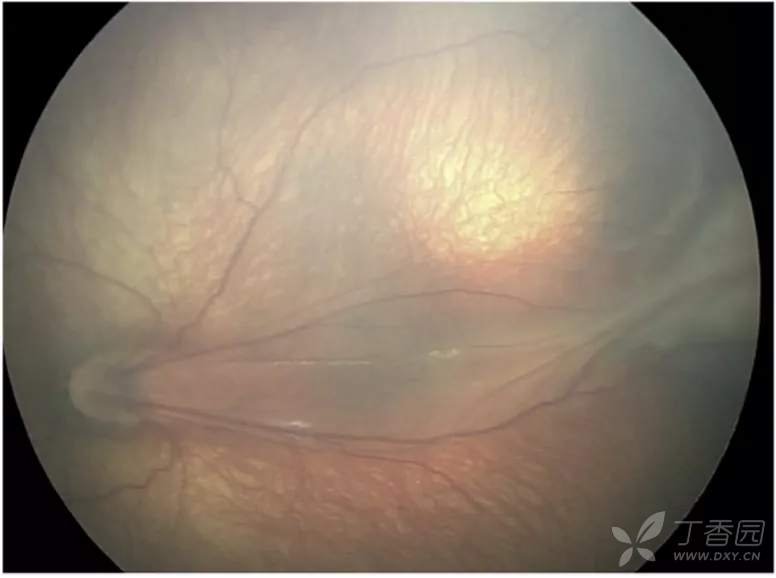

06、急性早产儿视网膜病变4期:部分视网膜脱离

图. 4A期, 视网膜外新生血管牵引可导致视网膜隆起(白点),中心凹(星号)未见脱离,视网膜外新生血管(白箭)可能较脱离区更周边。

图. 4A期ROP,周边嵴区域出现360°牵引性视网膜脱离。

急性ROP4期OCT图像

图. 4A期视网膜脱离:OCT可见中心凹视网膜附着(星号),视网膜内渗出(高反射点)、周边部视网膜脱离和视网膜劈裂。